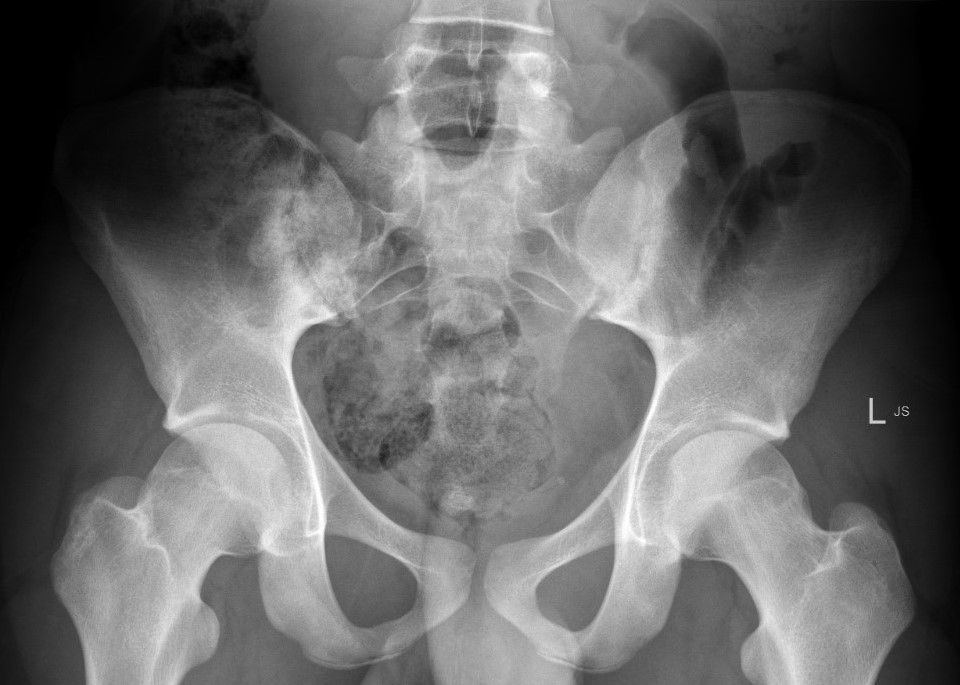

Sacro-iliac joint

- erosion / sclerosis / finally ankylosis

Hip & Shoulder

- concentric joint space narrowing

- bony ankylosis

- protrusio